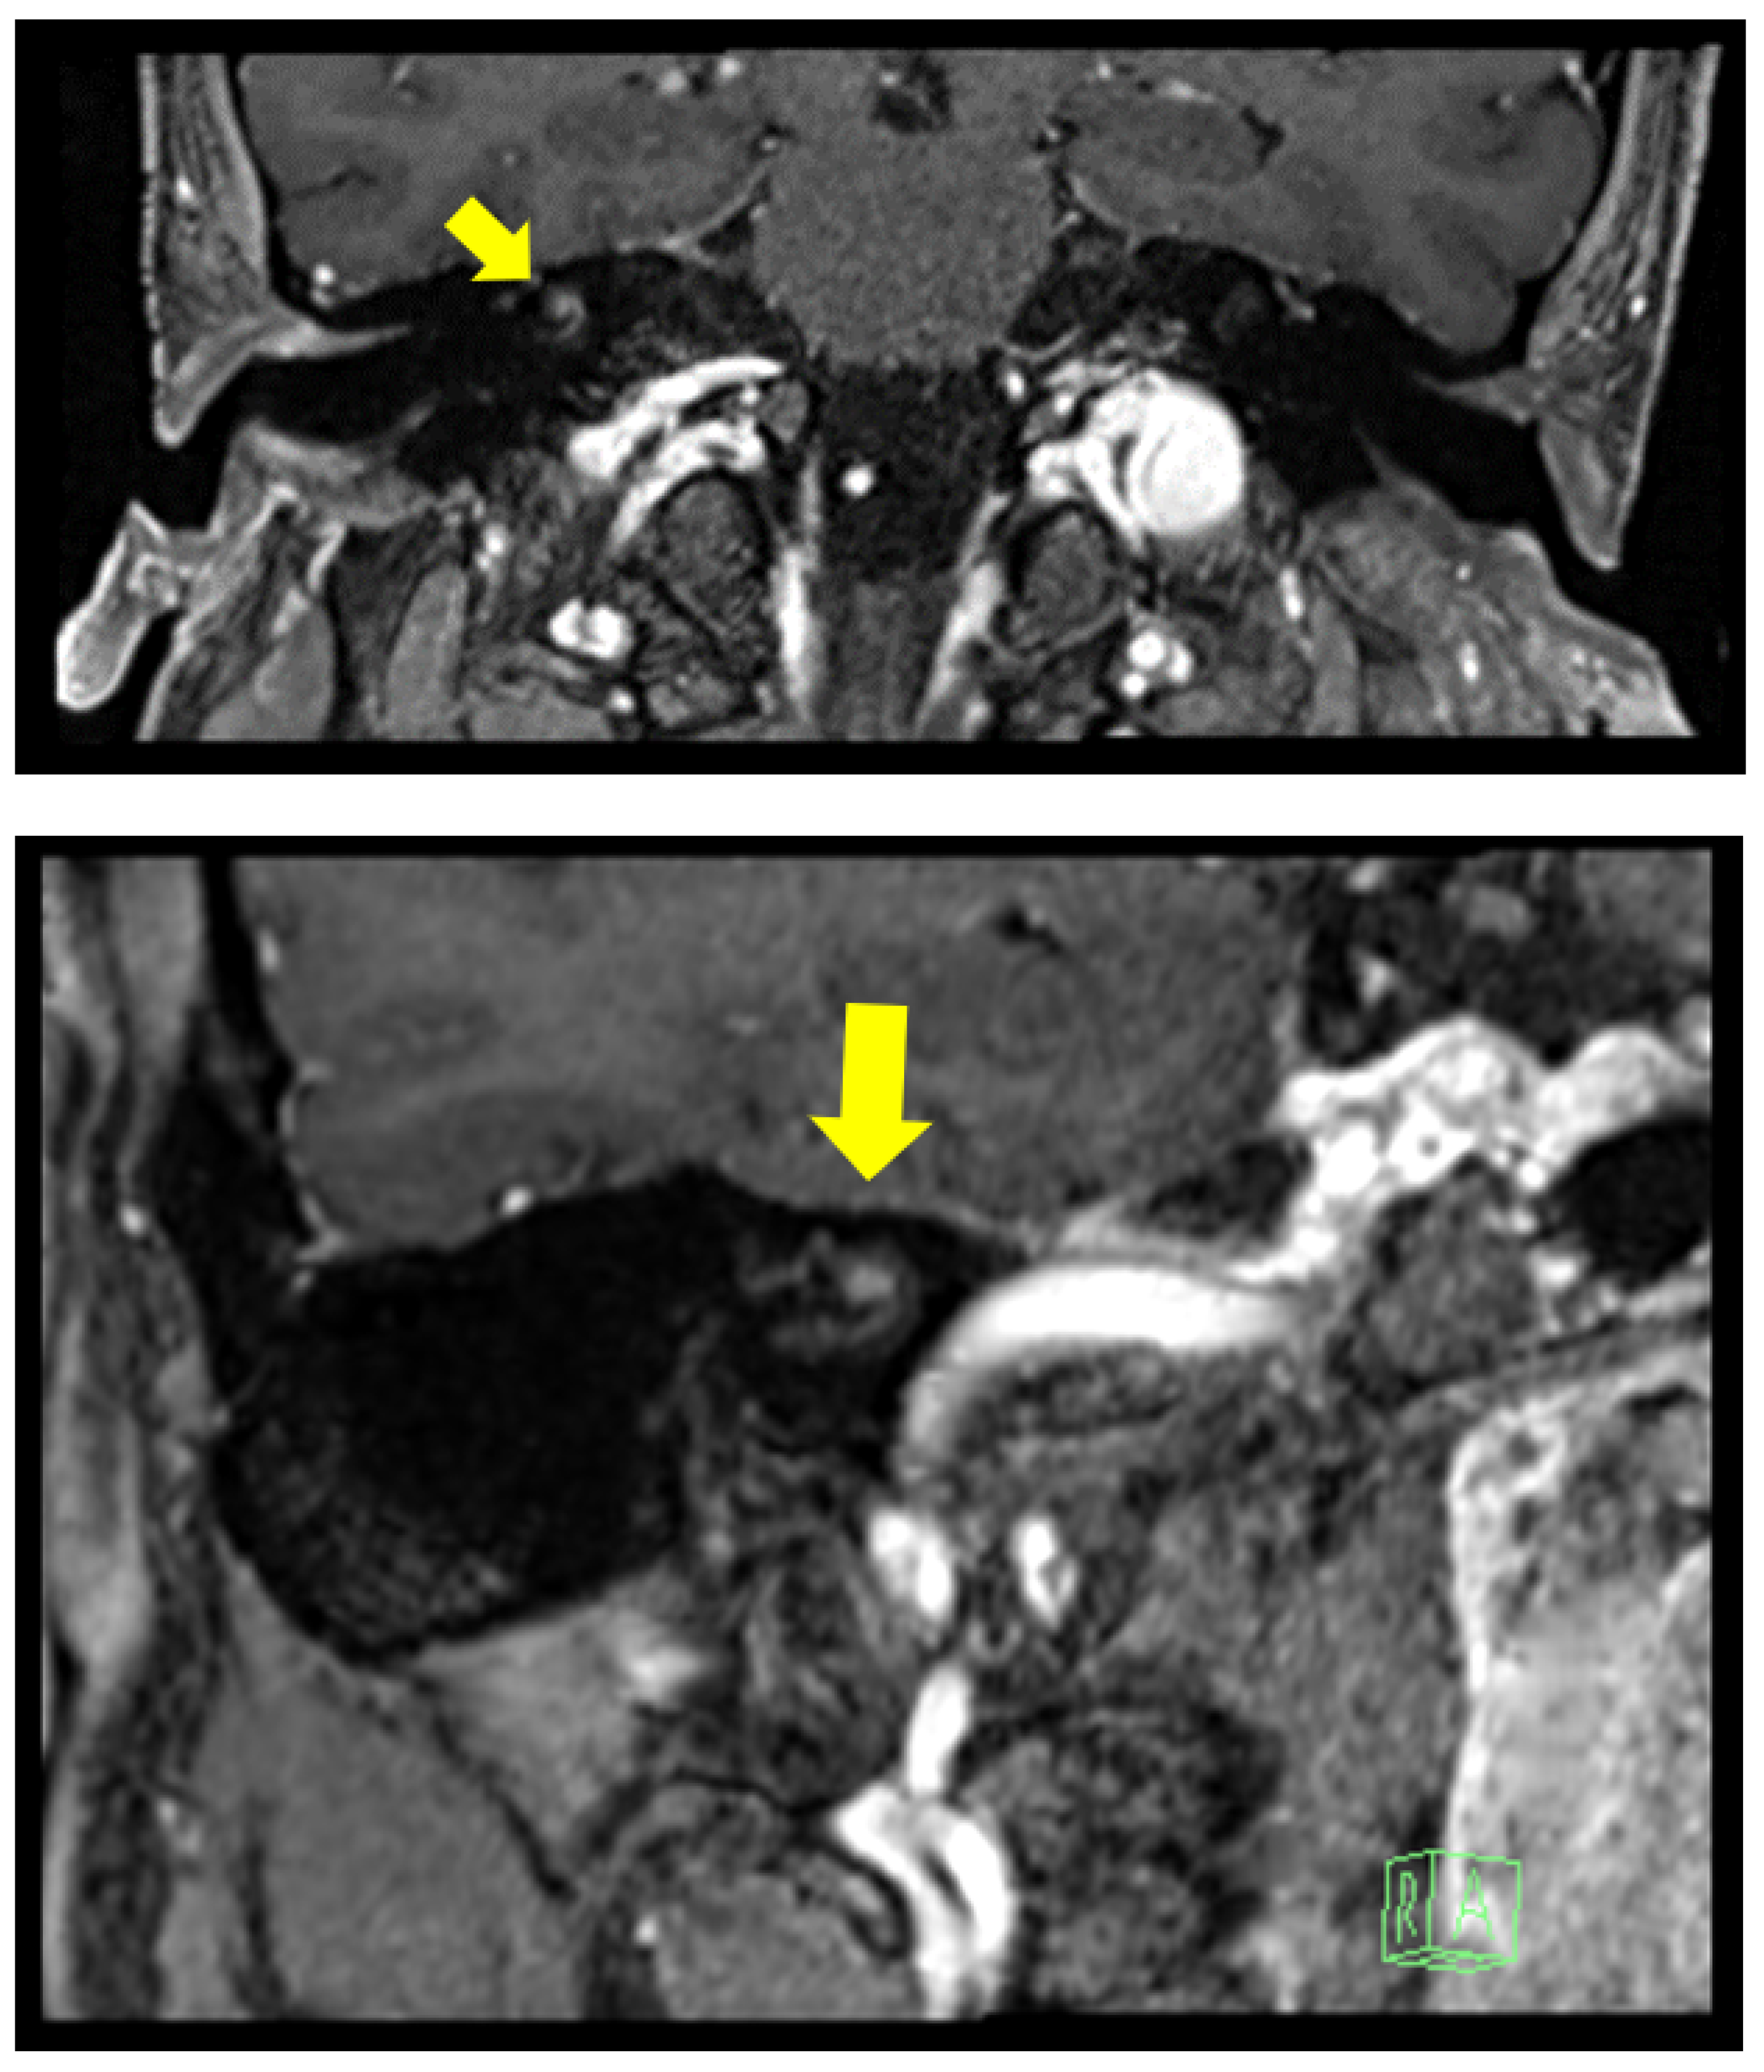

2.1. Clinical Case 1

2.2. Clinical Case 2